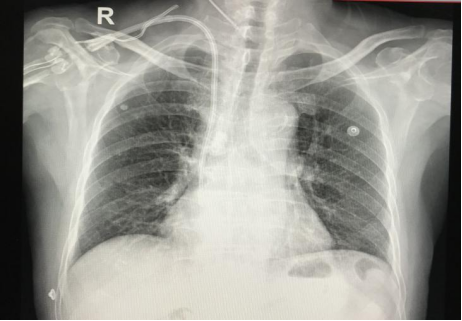

带Cuff的中心静脉导管是将特制的带涤纶套埋于皮下隧道,导管入颈内静脉,到达上腔静脉至右心房交界处而建立的血管通路。其优点为插入后即可使用,无血流动力学紊乱,无需长期多次内瘘静脉穿刺痛苦,较临时导管感染率低等。